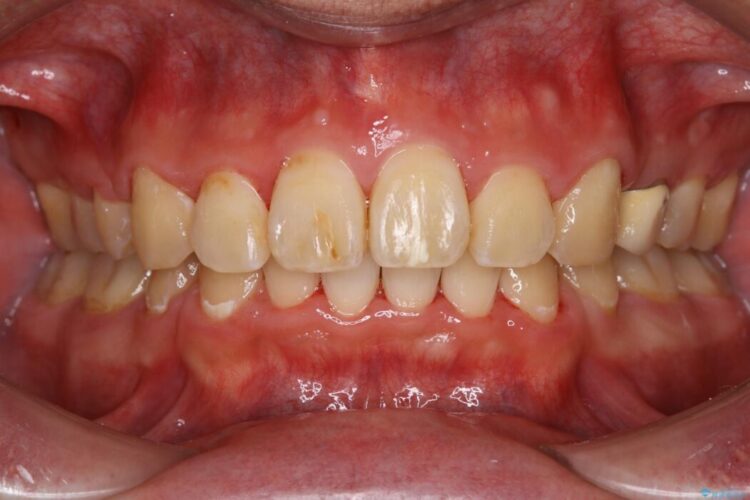

【30代男性】ワイヤー矯正で出っ歯とガタつきの改善

上の歯の出っ歯と下の歯のガタつきが気になるとご来院された患者様です。

治療後について

ワイヤー矯正、マウスピース矯正、それぞれの特性、得意な治療がありますので、患者様の状態に合わせた治療器具の選択が大事となります。